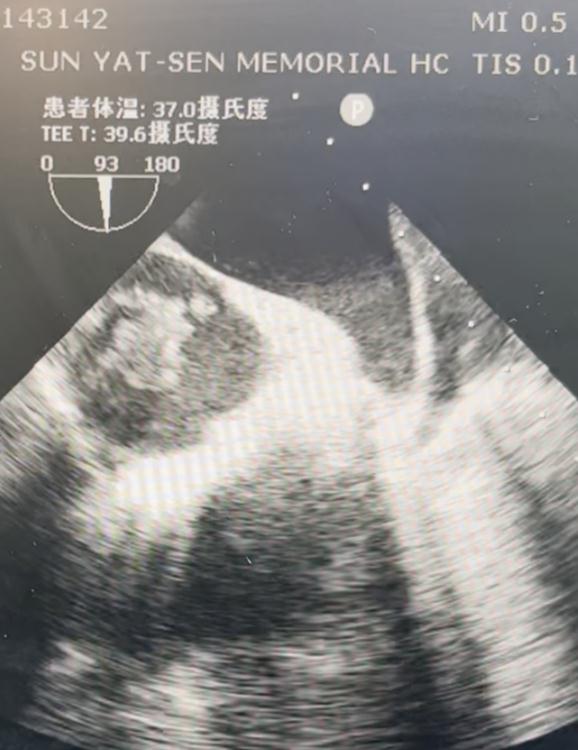

周晖副教授介绍,王女士心房内的瘤栓长达5厘米,随着心脏跳动不时探入心室,在超声监测下,心脏内巨大的瘤栓就如正在倒计时的“炸弹”,时刻威胁着王女士的生命。

术中经食管心脏超声监测

第四,术中超声动态监测瘤栓,体外循环机及ECMO机器随时待命,确保手术安全。麻醉科纪风涛副教授通过术中动态食管内超声监测心房内瘤栓变化,心血管外科梁石副教授准备好开胸手术,体外循环机及ECMO机器在手术室待命,应对任何意外变化。输血科赵祎莉主任作好充分的血源准备。